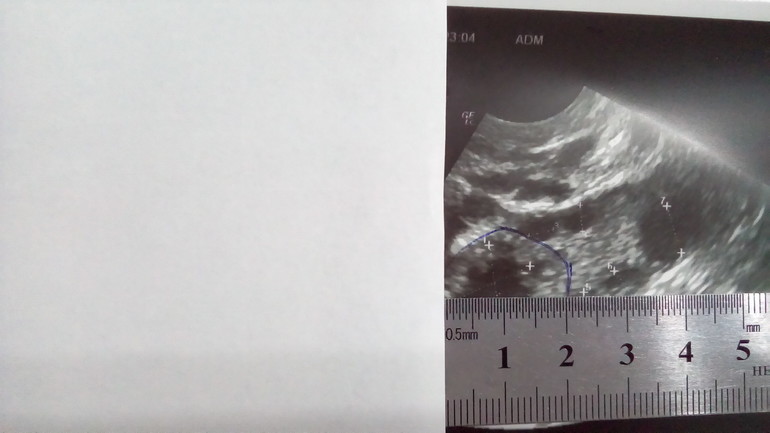

Фолликулометрия на 13 дц

ФолликулометрияУЗИ на 13 дц:

Эндометрий 10 мм

Свободная жидкость в позадиматочном пространстве в обьёме 10 мл

В ЛЯ 6 фолликулов: 3 мм, 3 мм, 3 мм, 3 мм, 4 мм, 7 мм

В ПЯ 7 фолликулов: 3 мм, 3 мм, 4 мм, 5 мм, 5 мм, 5 мм, 6 мм и ЖТ 15*14 мм

Узистка странно как то намерила ЖТ, она сама сказала, что размер указала внутри, а так оно больше.

Я попробовала измерить линейкой и оно около 20 мм вместе с жёлтым ободком.

Какой размер ЖТ считается правильным внутренний или полный?

P.S. Я уж поняла что на фото единица измерения другая, 1 см приравнивается к 1,3 см, вот она и разница видна. Значит всё правильно она померяла, внутренний диаметр ЖТ 15*14 мм, подрастёт ещё, надеюсь. На линейке 21 мм, а на самом деле 15 мм. Масштаб не 1:1.

Я уж поняла что на фото единица измерения другая, 1 см приравнивается к 1,3 см, вот она и разница видна. Значит всё правильно она померяла, внутренний диаметр ЖТ 15*14 мм, подрастёт ещё надеюсь.

На на линейке 21 мм, а на самом деле 15 мм